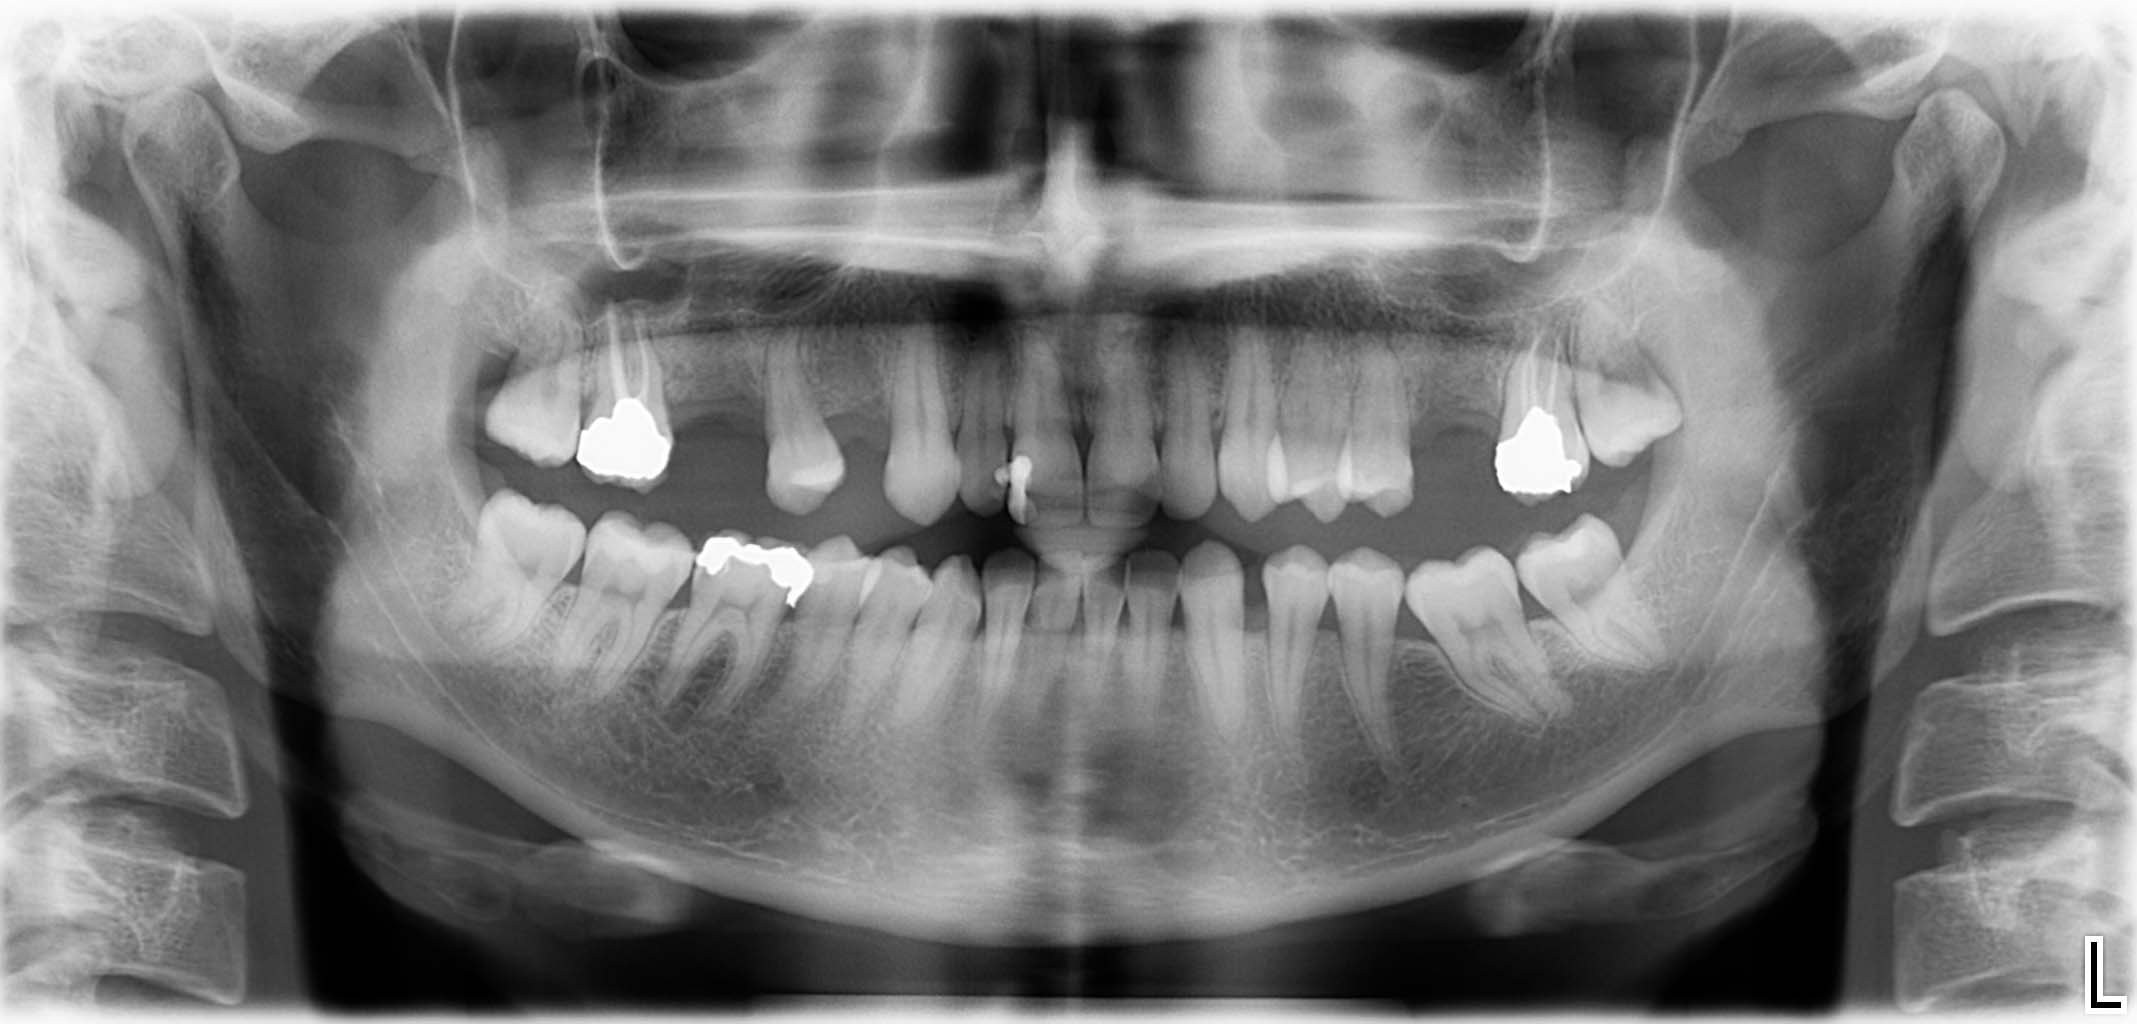

Erfolgreich implantierte Patientenfälle (klinische Fotos)